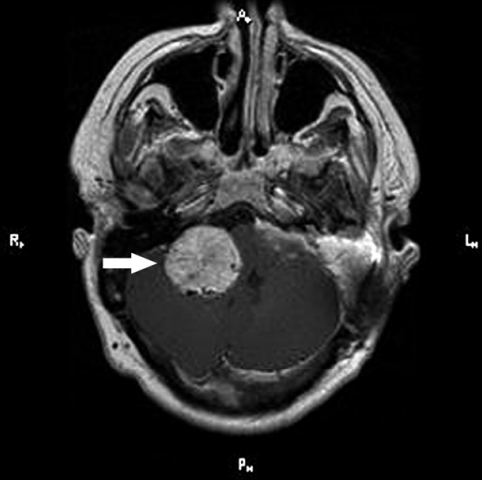

2型神經(jīng)纖維瘤病是以神經(jīng)系統(tǒng)中非癌性腫瘤的生長(zhǎng)為特征的疾病。與2型神經(jīng)纖維瘤病相關(guān)的較常見(jiàn)的腫瘤稱(chēng)為前庭神經(jīng)鞘瘤或聽(tīng)神經(jīng)瘤。這些生長(zhǎng)沿著將信息從內(nèi)耳傳遞到大腦(聽(tīng)神經(jīng))的神經(jīng)發(fā)育。在這種情況下,通常還會(huì)發(fā)現(xiàn)發(fā)生在其他神經(jīng)上的腫瘤。

2型神經(jīng)纖維瘤病的體征和癥狀通常出現(xiàn)在青春期或二十多歲,盡管它們可以在任何年齡開(kāi)始。前庭神經(jīng)鞘瘤常見(jiàn)的早期癥狀是聽(tīng)力下降,耳鳴(耳鳴)和平衡問(wèn)題。在大多數(shù)情況下,這些腫瘤會(huì)在30歲時(shí)出現(xiàn)在兩只耳朵上。如果腫瘤在神經(jīng)系統(tǒng)的其他部位發(fā)展,則其體征和癥狀會(huì)根據(jù)其位置而異。腫瘤生長(zhǎng)的并發(fā)癥可能包括視力變化,手臂或腿部麻木或無(wú)力以及腦部積水。一些患有2型神經(jīng)纖維瘤病的人也會(huì)在一只或兩只眼睛上出現(xiàn)晶狀體混濁(白內(nèi)障),通常是在兒童時(shí)期開(kāi)始的。